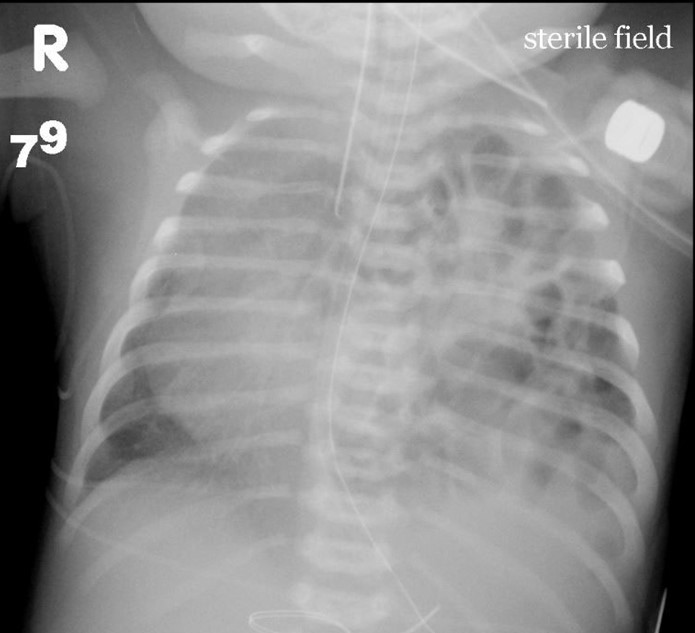

A newborn boy is evaluated in the delivery room 10 minutes after birth for increasing respiratory distress.  He was born at 38 weeks gestation by a forceps-assisted vaginal delivery complicated by a 2-minute shoulder dystocia.  The infant's mother did not receive any prenatal care.  Temperature is 36.8 C (98.2 F) , blood pressure is 70/40 mm Hg, pulse is 168/min, and respirations are 72/min.  Oxygen saturation is 82% on room air.  Physical examination shows grunting, nasal flaring, and cyanosis of the mucous membranes.  Chest x-ray is shown below: A newborn boy is evaluated in the delivery room 10 minutes after birth for increasing respiratory distress.  He was born at 38 weeks gestation by a forceps-assisted vaginal delivery complicated by a 2-minute shoulder dystocia.  The infant's mother did not receive any prenatal care.  Temperature is 36.8 C (98.2 F) , blood pressure is 70/40 mm Hg, pulse is 168/min, and respirations are 72/min.  Oxygen saturation is 82% on room air.  Physical examination shows grunting, nasal flaring, and cyanosis of the mucous membranes.  Chest x-ray is shown below:   Which of the following is the most likely diagnosis in this patient? A) Congenital diaphragmatic hernia B) Group B Streptococcus pneumonia C) Tension pneumothorax D) Tetralogy of Fallot E) Transient tachypnea of the newborn Which of the following is the most likely diagnosis in this patient?

A) Congenital diaphragmatic hernia

B) Group B Streptococcus pneumonia

C) Tension pneumothorax

D) Tetralogy of Fallot

E) Transient tachypnea of the newborn